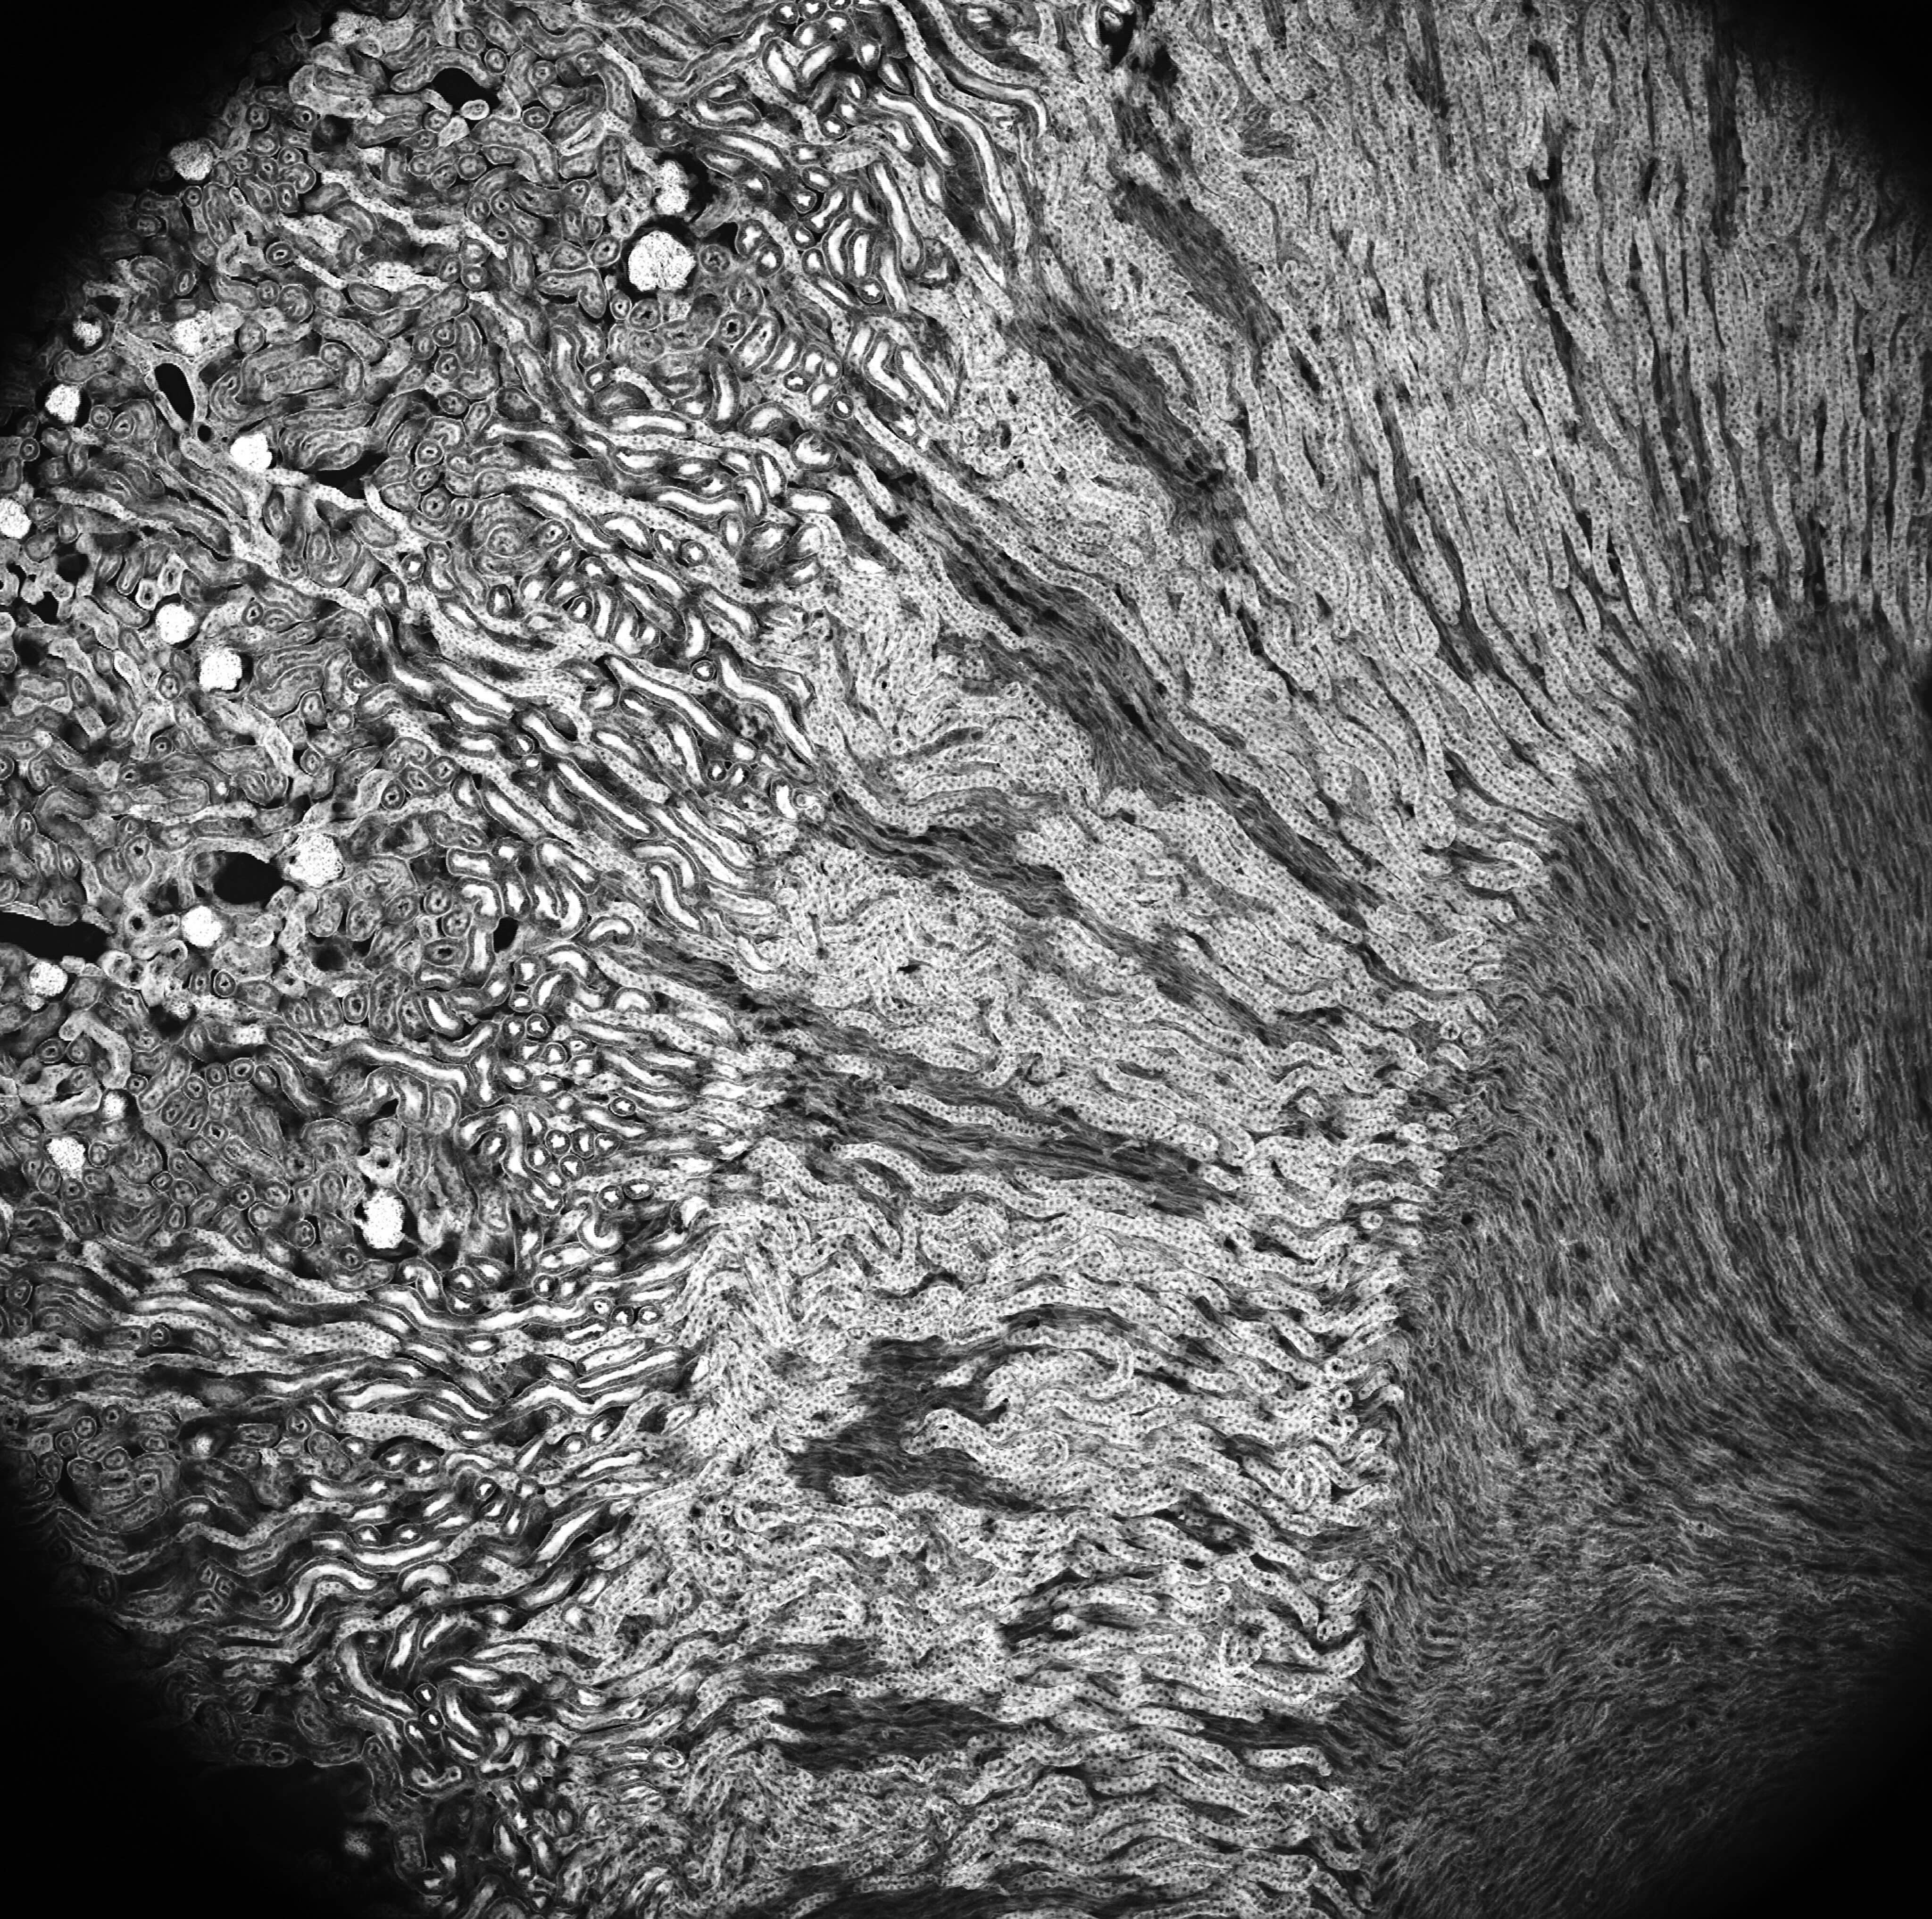

Image is an example from the Ventana Wide imaging system with the Cousa objective.

Field-of-view: 3.15 mm x 3.15 mm = 10 square mm

Imaged at 16,000 scan lines /s

4096 x 4096 pixels

Mouse kidney sample, Alexa Fluor 488 WGA, Alexa Fluor 568 Phalloidin, and DAPI.